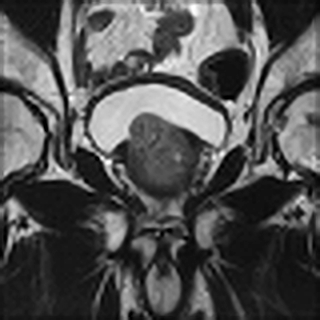

(a) Bicubic interpolation

Refer to caption

(b) Sparse Representation

(c) SRCNN

(d) SRResNet

(e) SRGAN 4x

(f) HR ground truth image

Figure 4: SR result for 4×4\times upscaling using- Bicubic interpolation, SRCNN, Sparse Representation, SRRestNet, and SRGAN

V-C Qualitative SRGAN Image Quality Assessment

Fig. 4 contains an example SR output for each method and the LR and HR images for reference. The LR image is severely pixelated and has no edge fidelity. While the image produced via bicubic interpolation has no pixelation, this method is still unable to preserve the high frequency information found in the ground truth image. The Sparse Representation method produces slightly better results than the previously discussed methods. However, the large amount of space and time overhead required by this model precludes it from clinical use. The SRCNN begins to show edge preservation, however the features within different regions of the output SR image are smoothed out. The SRCNN is especially biased toward smoothing the image because the network only uses MSE loss. The SRResNet has both MSE and perceptual loss yet fails to outperform the SRGAN. Clearly, the discriminator network seeks out the high frequency information that differentiates HR and LR images, thus forcing the SRGAN output to have far more high frequency details than the output of the SRResNet. The SRGAN 8x network is not able to maintain as high an edge fidelity as the SRGAN 4x network. This result is expected because the SRGAN 8x network is provided with far less information since the input LR image is a further 2x smaller in both dimensions (Fig. 5). Overall, in comparing the SRGAN to the other models, the outputs from the SRGAN are visually closer to the original HR ground truth images.